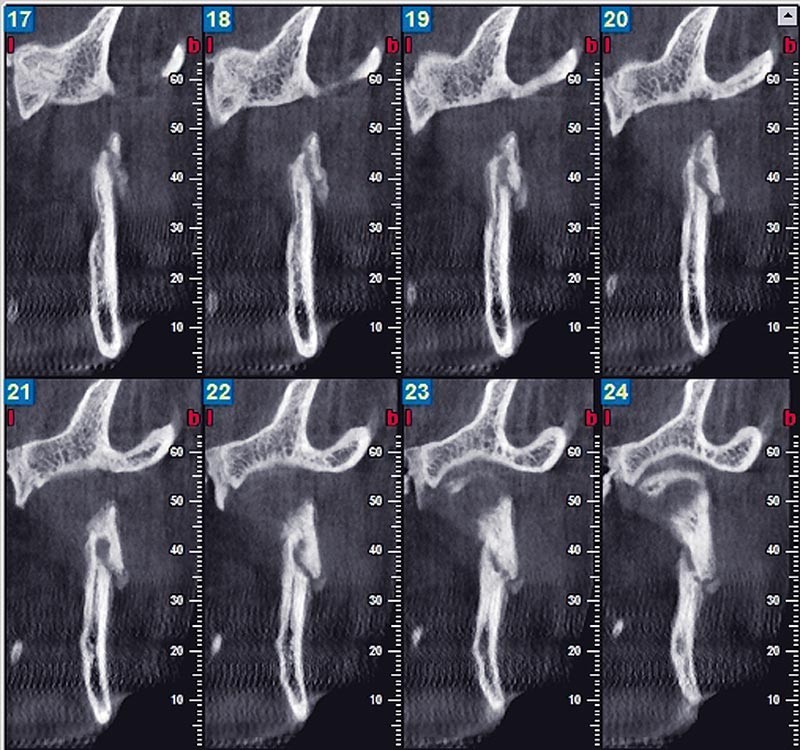

Comparée aux techniques radiographiques conventionnelles, comme la radiographie panoramique, la transcrânienne et les coupes Scanora, le cone beam permet une évaluation morphologique dynamique et surtout tridimensionnelle, par le développement de modèles virtuels en 3D, tout en délivrant une quantité considérablement moindre de rayons X. La prise de clichés est plus facile et plus confortable qu’au moyen de la tomodensitométrie (scanner), la qualité de l’image est bien meilleure et le coût en est nettement moindre [1]. Contrairement à la radiographie conventionnelle qui donne des images avec superposition de structures osseuses adjacentes, ce qui rend l’interprétation difficile et incertaine, la technique cone beam permet de visualiser clairement les ATM sans interférence de structures anatomiques avoisinantes [2].

Elle permet en outre de détecter les modifications osseuses mineures (indétectables au moyen des techniques radiographiques conventionnelles) [3]. La technique de reconstruction en 3D présente en plus un intérêt didactique, qui permet aux praticiens une meilleure compréhension de la situation par une visualisation spatiale de l’image.

Enfin, le cone beam est un moyen précis d’évaluation du volume osseux [3] pour établir, à titre indicatif, les modifications morphologiques du condyle résultant de diverses pathologies. Les données volumétriques obtenues sont utiles pour comparer les côtés gauche et droit de la mandibule et être en mesure d’évaluer l’asymétrie entre les deux condyles dans les divers types de malocclusion. Plus généralement, il rend possible la réalisation de coupes épaisses comme une reconstruction panoramique volumique ; la sélection des densités les plus élevées permet d’isoler les structures osseuses et dentaires [4].